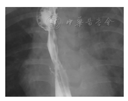

4例患儿中,2例(患儿1、3)在食管扩张术中发现右侧大量气胸,1例(患儿4)在术中可见胃镜进入胸腔,1例(患儿2)于术后第二天出现呼吸困难、发热及左侧气胸(图2),均初步诊断为食管穿孔;3例在24 h内诊断,1例在48 h内获得诊断。该4例患儿的具体资料见表1。

3例患儿经过3 d的治疗后体温完全正常,治疗后7~11 d首次行食管造影检查,治疗后7~13 d恢复经口喂养(患儿2在保守治疗7 d后食管造影检查仍可见少量食管漏)(图4),治疗后10~14 d出院;1例(患儿4)经保守治疗19 d后体温才完全恢复正常,治疗后23 d首次行食管造影检查仍提示食管漏,治疗后30 d行食管造影检查提示存在气管食管瘘并开始经空肠喂养,治疗43 d后出院。4例患儿随访时间范围为6~19个月(平均随访时间为11.5个月);其中1例(患儿1)再行食管扩张14次,目前可正常经口喂养,无进食呛咳及进食困难;1例(患儿2)再行食管扩张5次后出现呛咳表现,确诊为复发性气管食管瘘,并行胸腔镜手术修补,目前可正常经口喂养;1例(患儿3)因发展为长段型食管狭窄,目前经胃管喂养,需行食管替代治疗;1例(患儿4)确诊为复发性气管食管瘘,行胸腔镜手术修补后,可正常经口喂养。